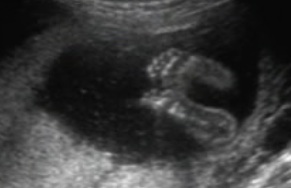

szégyenlős... :oops: ahogy forogtunk, úgy fordult ő is...

fenekét sürün láttuk, meg az összeszorított lábakat. Nevetett a dokicsaj is,azt mondta ilyen nincs :D :shock:

egészséges.Megvan mindene,jól fejlődik.De h fiú-e v lányzó nem tudni. doki szerint ha fiú lenne már tudnánk :lol: lányok szoktak igy bujdokolni :wink:

Kép :oops: :roll:

Kép